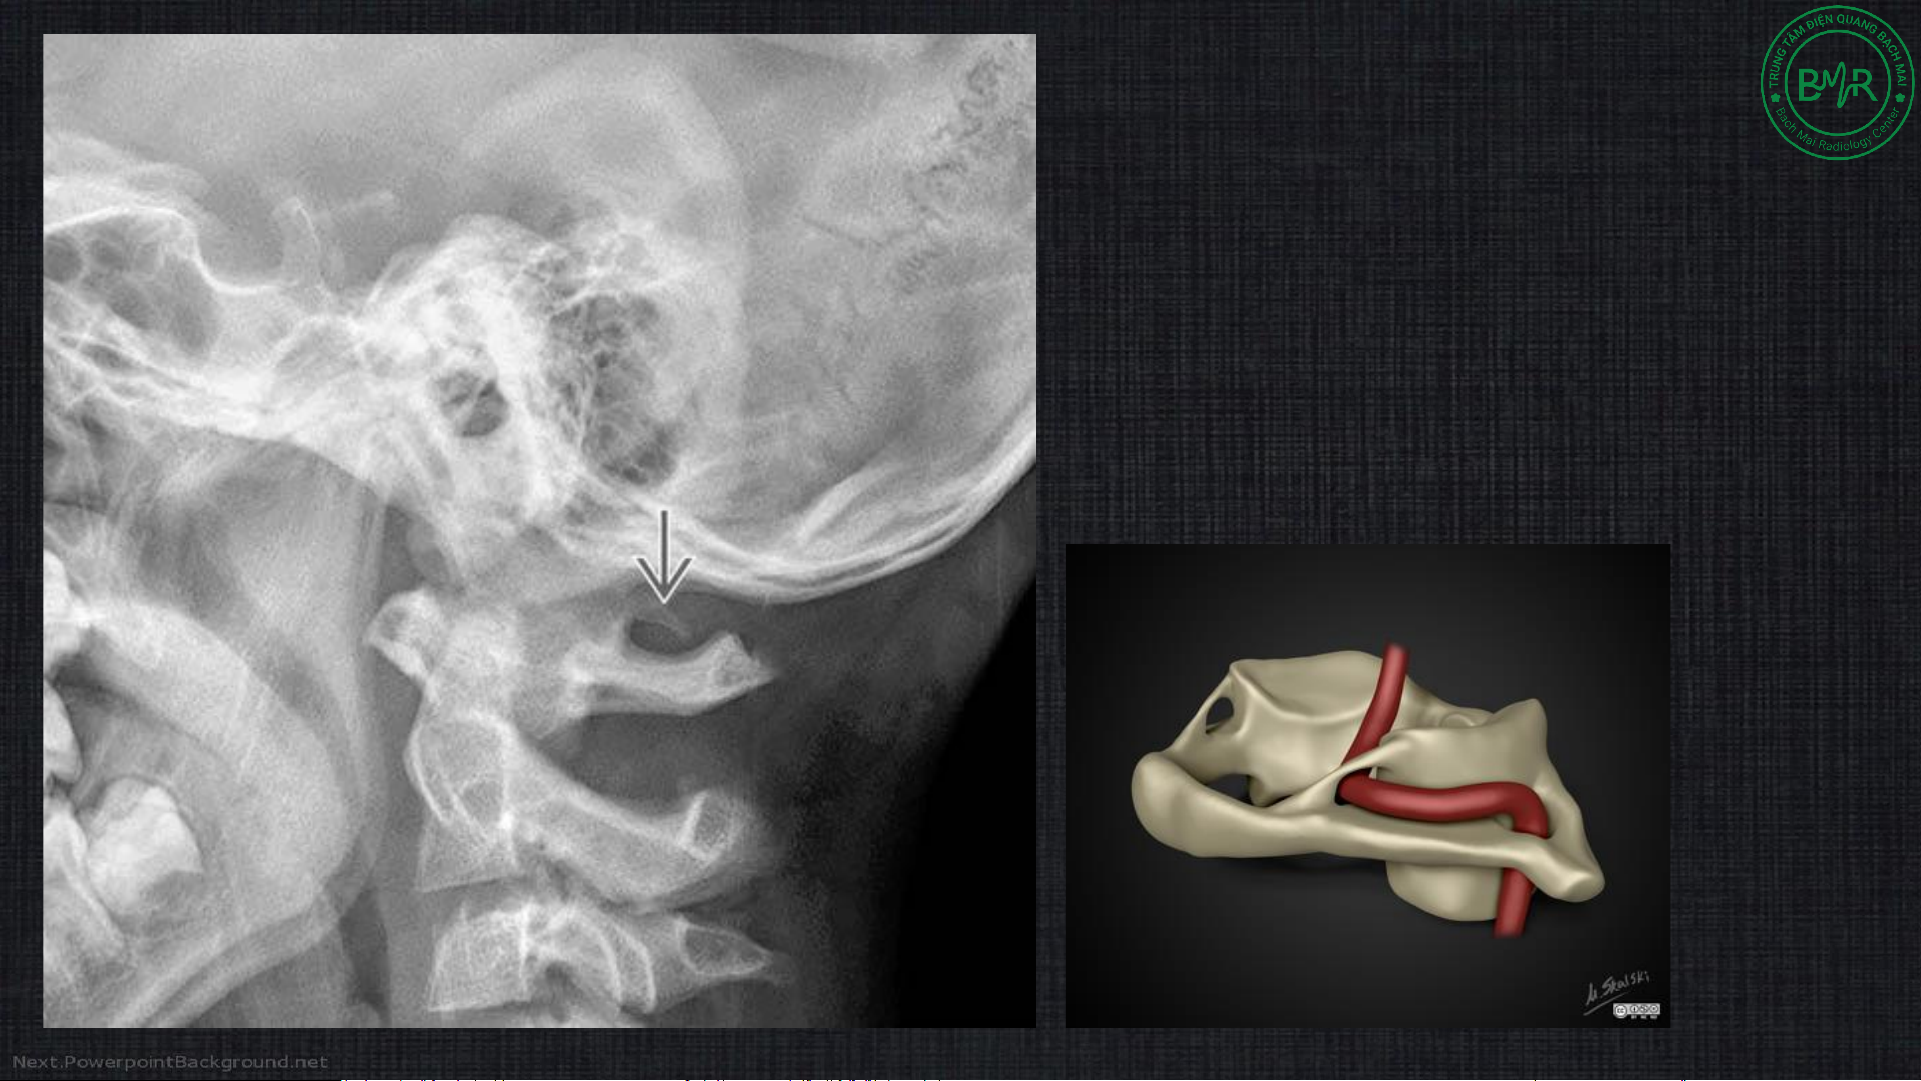

Ponticulus posticus (bất thường Kimmerle) •

Hình thành cầu xương nhỏ phía

sau do vôi hóa màng chẩm – đội •

Hẹp đoạn V3 ĐM đốt sống khi đi qua C1